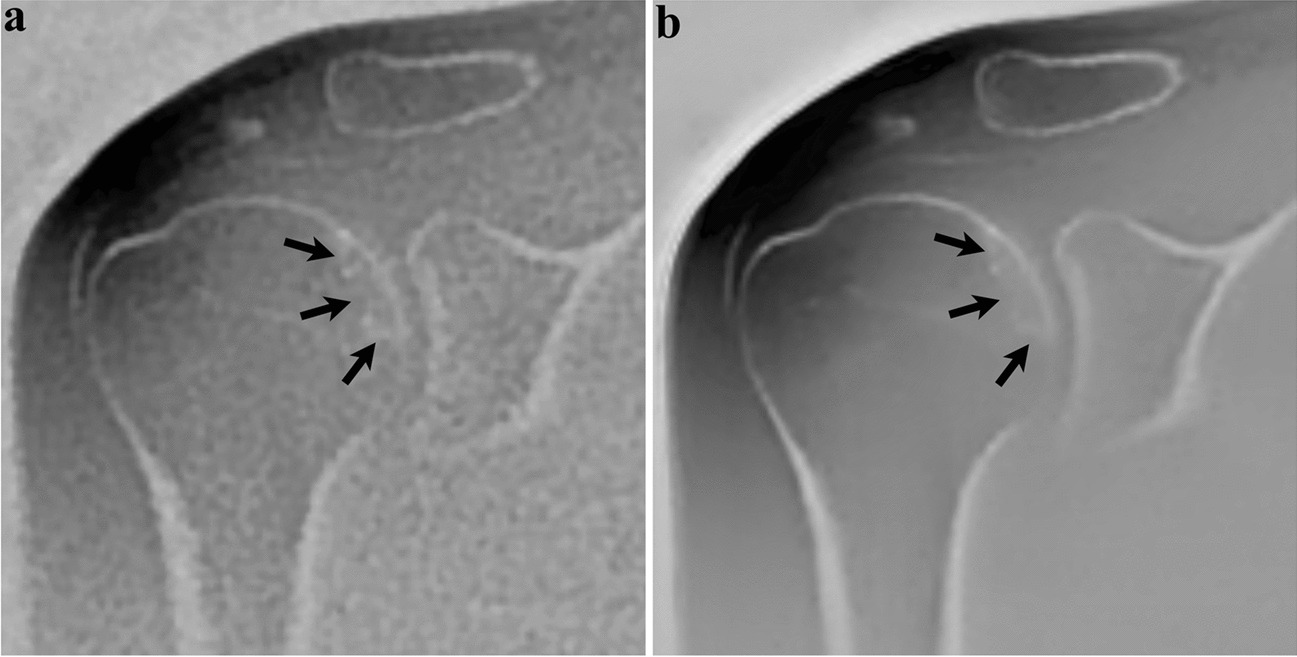

Fig. 5

Forty-three-year-old woman with facioscapulohumeral muscular dystrophy, no history of trauma. Coronal ZTE image reconstructed with the SOC method (a) shows sclerotic changes (arrows) in the subchondral bone of the humeral head. On the same image processed with DLRecon (b), the linear characteristic of sclerosis (arrows) becomes more conspicuous, consistent with a subchondral insufficiency fracture